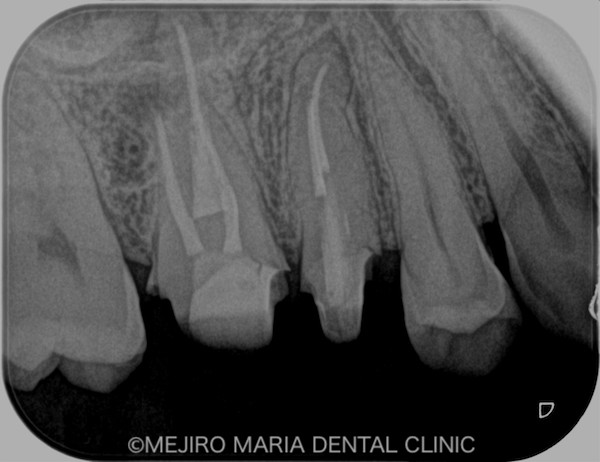

術後3ヶ月の経過は良好だったため、最終補綴処置を完了し、その後1年間、経過を確認しました。その結果、右上6番の歯に確認できていた病変も消失し、現時点は予後良好と判断しています。